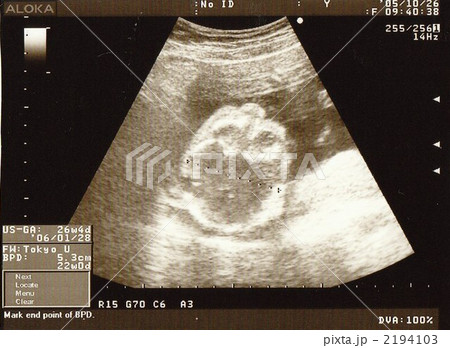

妊娠22週0日 22w0d の超音波 エコー 写真

22週のエコー写真。 おなかのなかで手足を動かしたり回転したりさまざまな動きをします 画像提供:丸茂レディースクリニック 身長は約25~27cm、重さは約450~550gになりまし